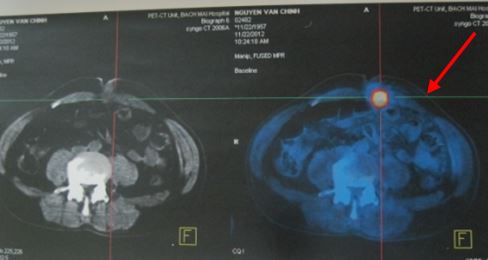

Hình 2: Khối thành bụng tăng hấp thu FDG (mũi tên) trên hình ảnh PET/CT.